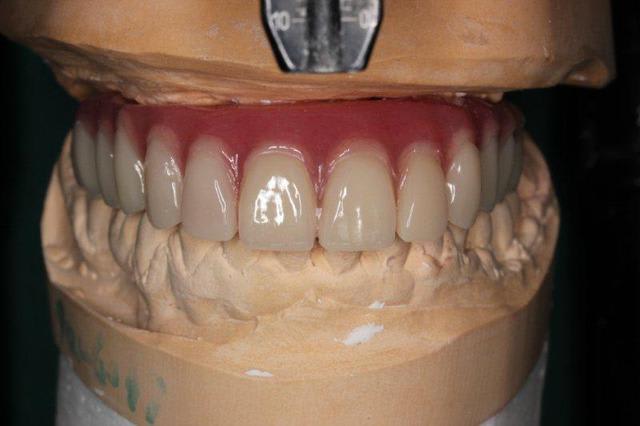

P'tite question, les vis qui tiennent la prothèse en place, sont des vis " plates", simple rainure.

L'axe de certains implants semble un peu trop palatin, mais bon, il n'y a pas de nonos...

1. C est toi qui es malhabile... Rien de plus simple : tu mets ttes tes vis ds la puits, tu les recouvres d homéoplasmine pour les empêcher de tomber hors des puits, tu poses en bouche et tu passes ton tournevis ds homéoplasmine pour visser Très simple et très efficace :-))))

2. Effectivemeznt les plaques zygomatiques ont des émergences palatines mais au définitif j ai ôté les piliers prlongateurs de 3.5 mm et du coup même si sortie palatine plus aucun "débordement" du puits de vissage en dehors de l arcade...

3.Ca fait 18 mois que les implants sont en charge donc tu as déjà une idée mais de manière générale ça fonctionne aussi bien qu pilotis à la mandibule... Un petit coup de waterpik léger et qques bains de bouches suffisent à entretenir tout ça correctement

Regarde le provisoire de la MCI : les émergences des plaques au niveau molaires font des bombés hors arcades suite à la pose de piliers monobloc de hauteur 3.5 mm

On pose ces piliers car il faut pouvoir retrouver facilement les têtes d implants 72 h plus tard pour poser la prothèse de transition